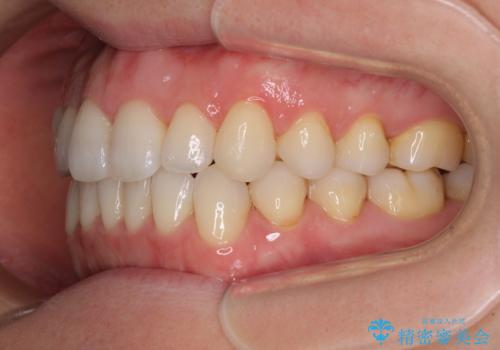

前歯の叢生とオープンバイト インビザラインでの矯正治療

- 前歯の開咬を気にして来院された患者様です。

開咬の治療は、前歯を閉じるように動かすとともに、上下臼歯を圧下(骨内にめり込ませる)させることで進めて行きます。

インビザラインは臼歯の圧下を効果的に行えるため、インビザラインを用いて矯正治療を行うこととしました。

オープンバイトは舌の突出癖により誘発され、治療後も突出癖が残っている容易に後戻りしてしまいます。

治療期間を短縮するためにも、舌突出癖の改善が極めて重要となります。